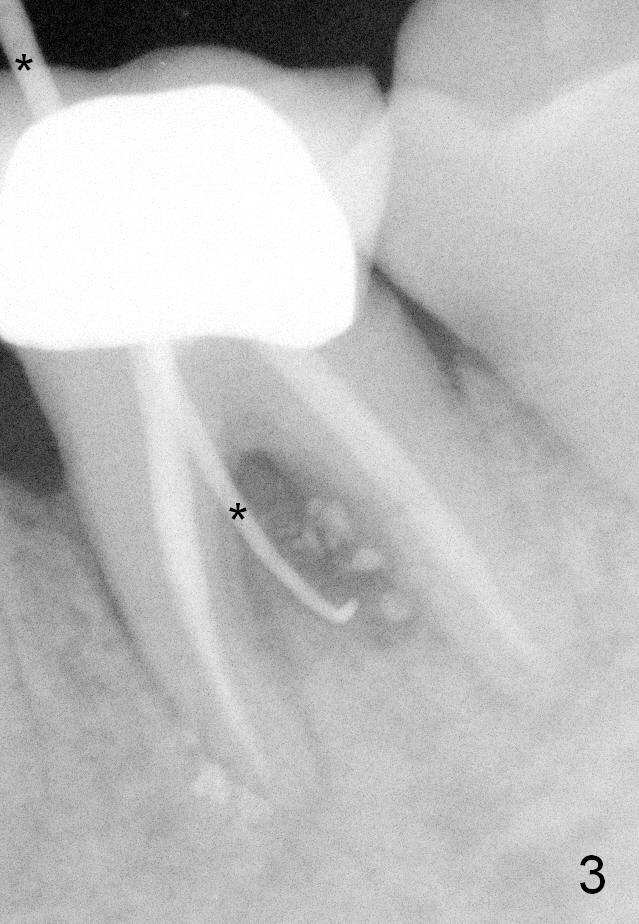

A 59-year-old lady has history of periodontal disease and bruxism. The tooth #19 has pulpitis after unsuccessful DO composite (Fig.1 *) and requires root canal therapy (Fig.2). Six months later, a fistula is found to communicate with the furca (Fig.3 *: gutta percha). Less than 3 years, the furca enlarges with symptoms of infection (Fig.4 *). She works out of state. The Principle of No Implant, No Extraction is adhered. Since she is of short statue, the bone height is relatively limited. A 6x14 mm tissue-level implant is appropriate (Fig.5, one piece). Sensor 1 may be proper for her small mouth. When the bottom of the socket is large and close to the Inferior Alveolar Nerve, can an immediate implant be placed?